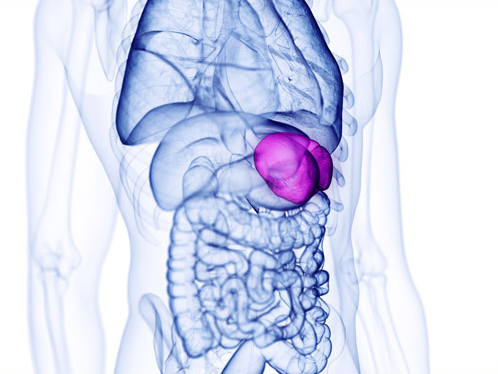

脾臓は赤血球を壊す・血小板を貯蔵する・抗体を作るなど様々な働きをしています。消化器系、栄養吸収不良や慢性疲労の改善、婦人科の疾患に関連が強いです。

鼠径部

脾経では鼠径部の鬼門を開くことがポイントです。イメージとしては、この場所に穴を開けるようにと意識しながらおこなうことで、気門が開きやすくなり、次に経穴を治療するときにより効果を発揮します。